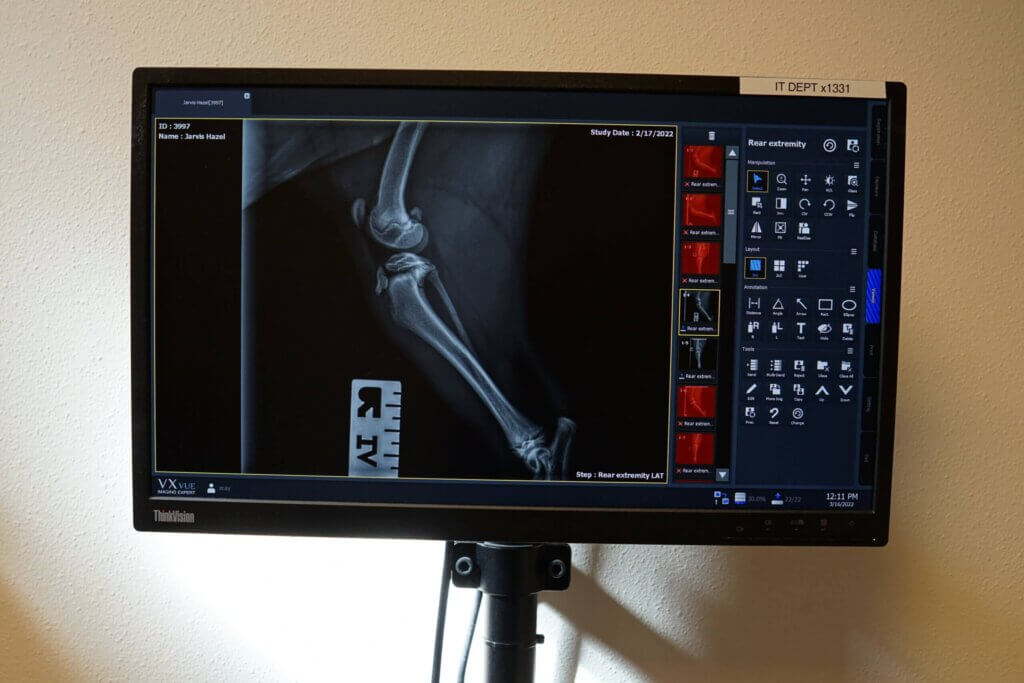

Veterinary X-Ray and Diagnostic Care

Precision Imaging with Veterinary X-Ray and Diagnostic Care Our on-site, digital X-ray equipment provides high quality radiographs to aid in the diagnosis of many disorders.We use digital radiograph equipment to provide better diagnostic quality, save time, and reduce stress for your pet. Specialty diagnostics, such as adbominal ultrasound and echocardiography, are available at our clinic […]